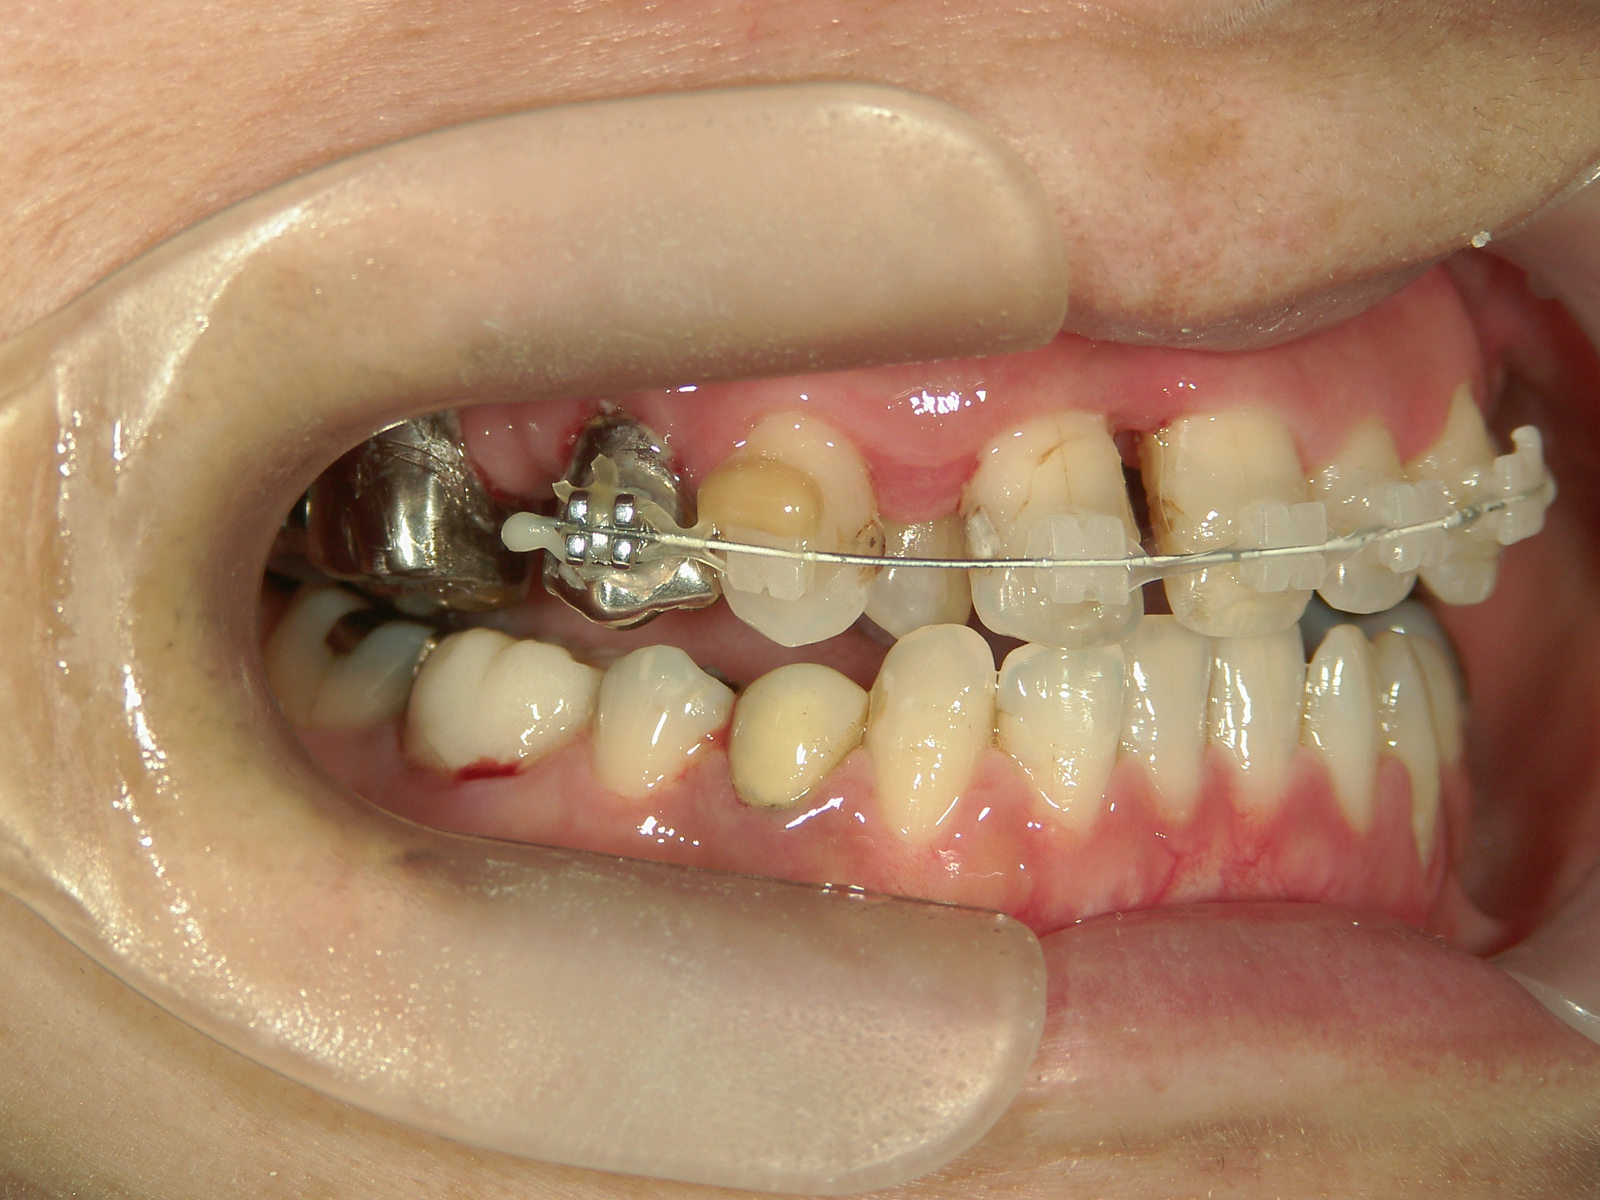

右下第一小臼歯(1本)、右下親不知(1本)を抜歯。

右下第一大臼歯をセラミックへ変更。

上顎骨切断OPE、矯正装置(MSE+フェイスマスク)、ワイヤー矯正を併用。

②右上前歯が内側に入っているため、歯列に入る隙間を作るためにワイヤー矯正を併用し、右上前歯を出しました。